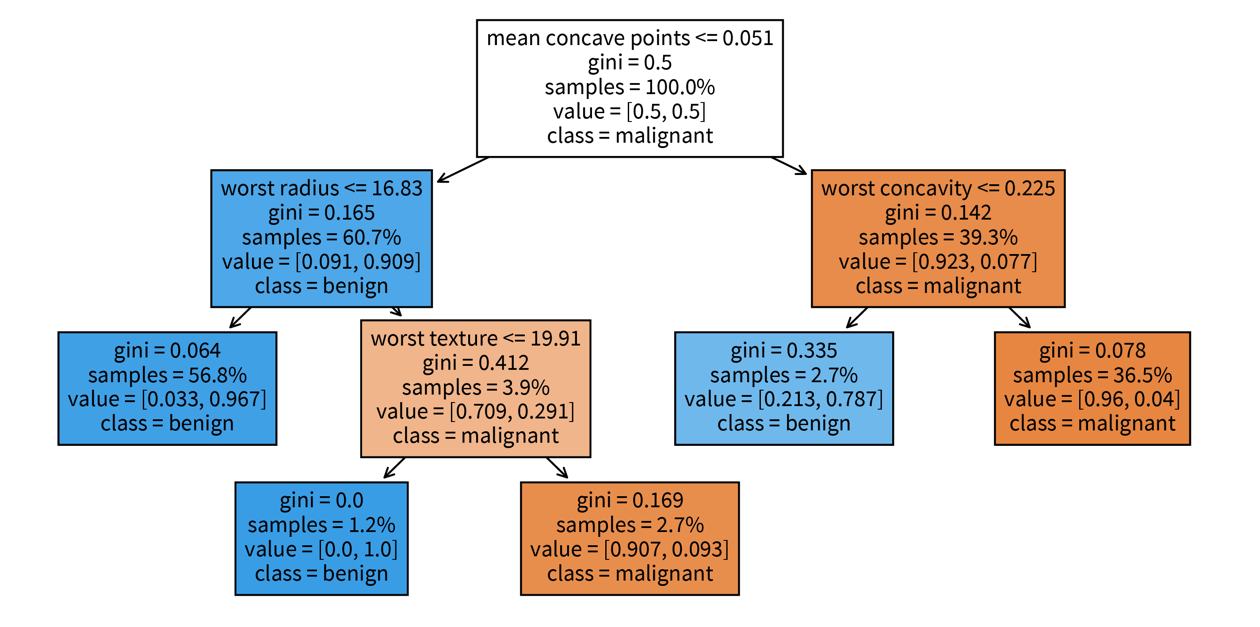

Explaining individual predictions: retrace decision path (in a single tree).

sklearn. The decision tree has its root at the top (where we start when predicting for a new sample) and the leaves (i.e., those nodes that don’t branch off anymore) at the bottom (where we stop and make the final prediction). Each node in the tree shows in the first line the variable based on which the next split is made incl. the threshold value (except for leaf nodes), then the current Gini impurity (i.e., how homogeneous the labels of all the samples that ended up in this node are; this is what the decision tree internally optimizes, i.e., notice how the value gets smaller on at least one side after a split), then the fraction of samples that ended up in this node, and the distribution of samples for the different classes (for a classification problem), as well as the label that would be predicted for a sample at this point. So when making a prediction for a new sample with a decision tree, we start at the root node of the tree and then follow the branches down depending on the sample’s feature values until we reach a leaf node and would then know exactly based on which feature thresholds the prediction for the sample was made.Global interpretation: a trained decision tree or random forest has an attribute feature_importances_, which indicates how much each feature contributed to reducing the (Gini) impurity. This is related to the position of the feature in the tree and how many samples pass through the respective node.